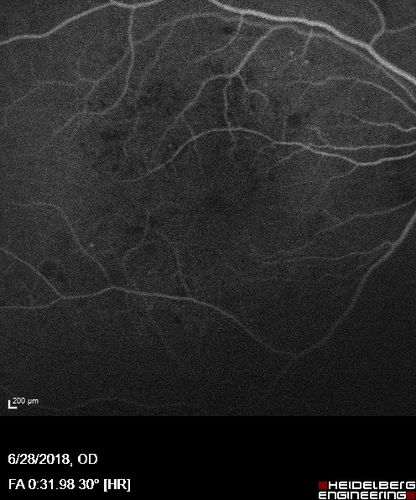

Diabetic Macular Edema with Exudates

Patient did not want injection therapy and did well with laser